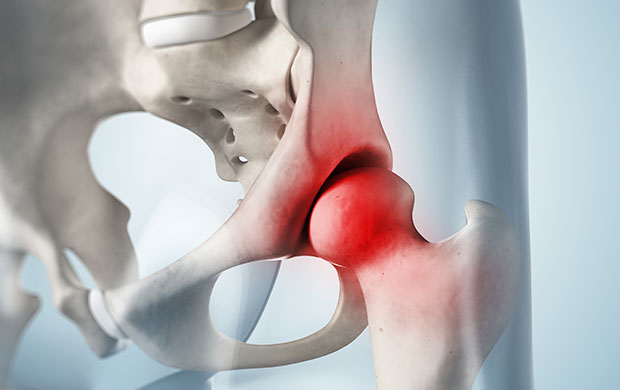

뼈가 과도하게 튀어나와 고관절 충돌이 발생합니다. 비구와 대퇴 경부가 선천적 또는 후천적으로 커져 과도한 스트레칭이나 운동으로 충돌하며 고관절 통증 증상을 유발합니다. 고관절 충돌 증후군으로 인해 고관절 통증 증상이 악화되면 비구순의 파열이 일어나고 관절 연골을 손상시킵니다. 심하면 퇴행성 고관절염에 이를 수 있습니다.

무혈관성 괴사란 혈액 순환 장애로 인해 혈액 공급이 원활하지 못하여 뼈가 썩는 병입니다. 대퇴골두 무혈관성 괴사는 허벅지 뼈, 즉 대퇴골의 머리 부분에 피가 통하지 않아 이 부분이 괴사 하게 되는 것입니다. 대부분 30~50대에게 발생하고, 여성보다는 남성에게 더 많이 발생합니다. 약 60% 이상은 양쪽 고관절의 대퇴골두 무혈관성 괴사를 겪습니다. 대퇴골두 무혈관성 괴사를 일으키는 위험 인자로는 음주, 부신피질 호르몬 투여, 고관절 부위 외상, 잠수병, 통풍, 혈청지질 이상, 만성 신질환, 만성 췌장염 등이 있습니다. 이 중에서도 음주와 부신피질 호르몬제가 전체 원인의 90% 정도를 차지합니다.